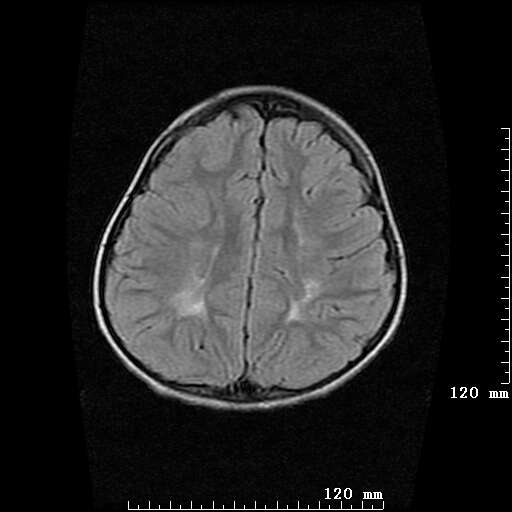

女,7岁,三岁才说话、走路。现智力尚可,走路不稳。临床怀疑大脑发育不全。

考虑 脑白质发育不良

脑折质变薄,双侧侧脑室稍扩张,支持考虑脑折质发育不良

侧脑室周围白质软化症。

考虑胼胝体发育不全,髓鞘形成不良。

支持考虑胼胝体发育不全,髓鞘形成不良。

脑裂畸形伴灰质异位

侧脑室周围白质数量减少,侧脑室不对称性扩大,左侧侧脑室后角呈方形改变,脑沟加深,结合临床考虑脑室周围白质软化症(pvl)。期待结果!

只看出灰质异位

支持脑白质发育不良。